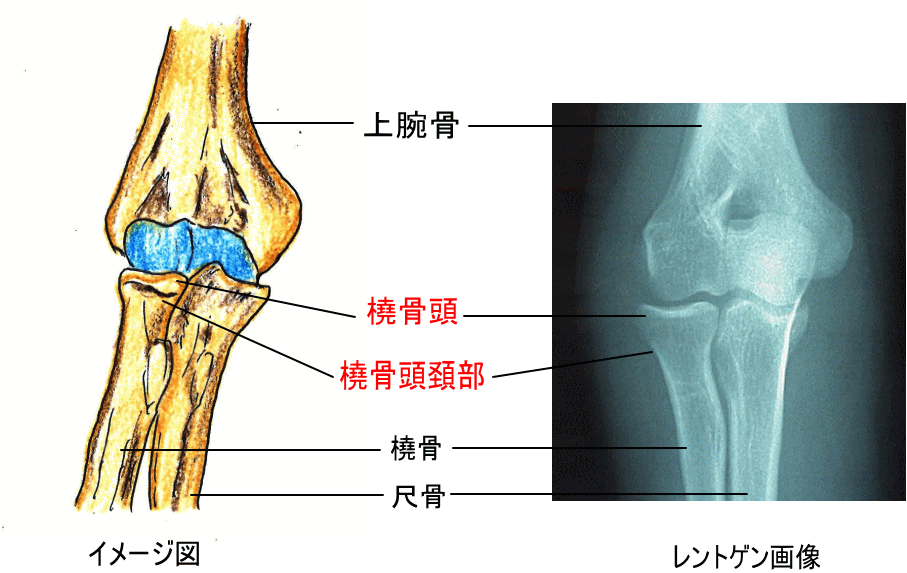

2.橈骨頭骨折(とうこつとうこっせつ)

前腕の橈骨の肘に近い部分が骨折するケースで、成人に多く、手をついて転倒した際に発生します。肘の曲げ伸ばしや手首の回旋が困難になることがあります。